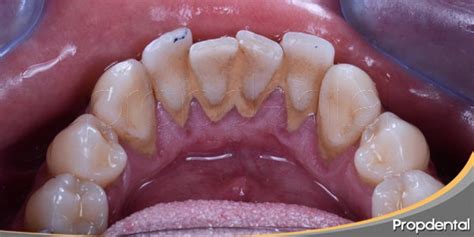

La anatomía oral explica por qué el sarro duro detrás de los dientes inferiores es tan común. Las glándulas sublinguales y submandibulares, ubicadas debajo de la lengua, secretan constantemente saliva rica en minerales directamente hacia la superficie lingual de los incisivos inferiores.

La superficie lingual de los dientes inferiores representa una de las zonas más desafiantes para mantener una higiene bucal adecuada. La posición de la lengua, la limitada visibilidad durante el cepillado y la dificultad para maniobrar el cepillo en esta área contribuyen a una limpieza incompleta.

El sarro sobre la línea de las encías, también denominado cálculo supragingival, es amarillo o tostado. El cálculo subgingival es el sarro que aparece debajo de la línea de las encías, el cual puede ser marrón, negro o verde.

El sarro puede acumularse por encima (supragingival) o por debajo (subgingival) de la línea de las encías.